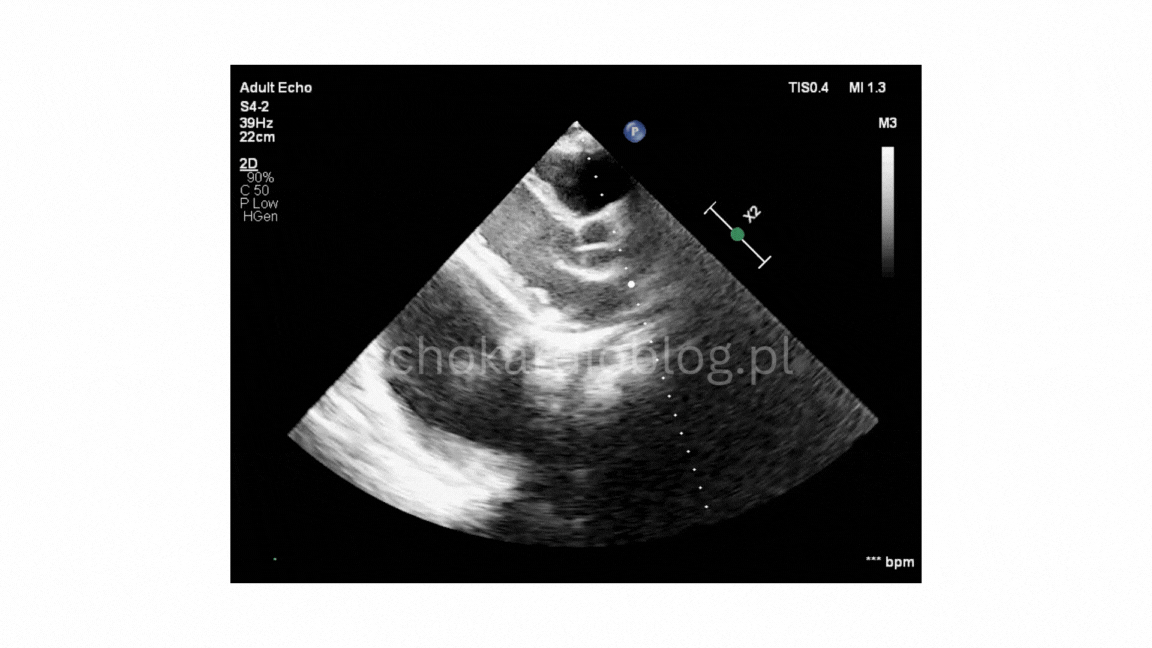

Prezentuję dwa przypadki pseudodyskinezy u pacjentów z marskością wątroby z wodobrzuszem:

przypadek 1 – silnie wyrażona jest pseudodyskineza i

We present two cases of pseudodyskinesia in patents with liver cirrhosis and ascites:

Case 1- marked pseudodyskinesia, and